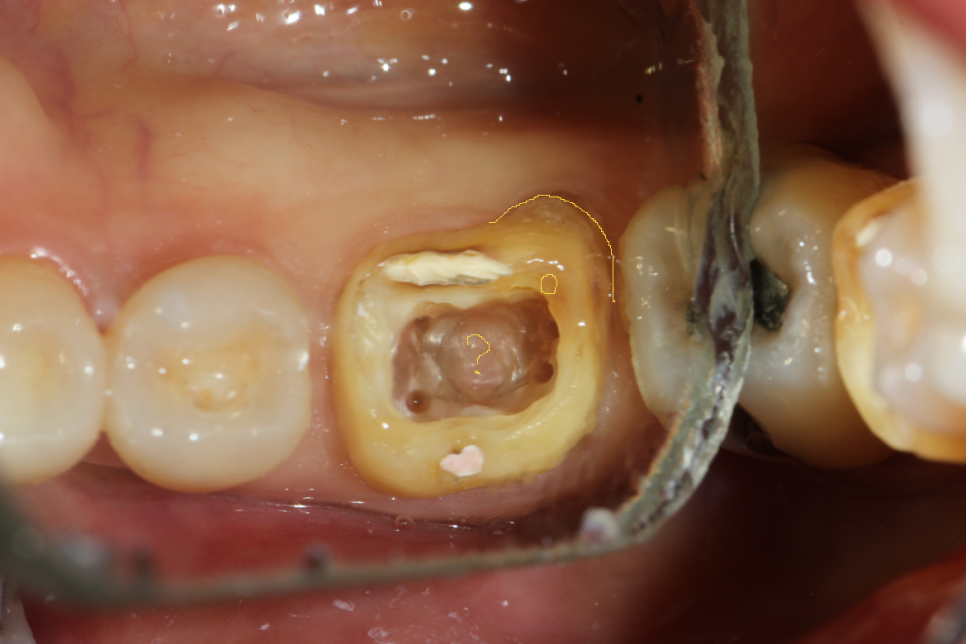

그리고 아래 두 장은 블로그에 올리지는 않았었지만, 저번 주에 기존 크라운 벗겨낸(그래서 프렙이 돼있다) 하악 제1대구치. 디스탈 근관 2개 다 찾았는데 드러난 DL치근 위치가 너무 돌출되어 있어서 해당 위치에 근관이 하나 더 있을 것으로 예상했었다. 그래서 이번 주 예약에 엔도Z버로 확장해 보니 실제로 근관 하나가 더 나왔다. 사실 이 치아는 처음엔 근관 찾으려고 찍은 사진이 아니고, 크라운 벗기고 AO 하니까 와동 바닥에 타DC에서 퍼포 시켜놓고 리페어를 했는지 도대체 알 수가 없는 치질 아닌 웬 이상한 게 있어서 찍어놓은 것이다. 근데 이게 뭘까~ 하고 사진을 가만 보다 보니 갑자기 디스탈에 근관 하나 더 있을 것 같아서 체크해놨었던 케이스.

EzDent에 그린 그림 (노란 선) 캡쳐

평소 진료하다가 이상한 게 있으면 DSLR로 찍어서 이렇게 EzDent(영상 프로그램)에 표시를 해놓는다. 혹시 다음번 내원하셨을 때 마침 내가 바빠서 대표원장님이 이 환자를 보게 되면 대표원장님께서 참고하실 수 있도록 찍기도 하고, 내가 다음번에 까먹을 수도 있고, 또 무엇보다 나 스스로 기록해 놓기도 좋고 해서 특이한 게 있으면 꼭 DSLR로 임상사진을 채득해 놓으려고 한다. 어디선가 구내 DSLR 촬영도 수가 산정을 해야 하는 거 아니냐고 하던데, 솔직히 나도 그 의견 지지한다💥 정말 필요한 일이야.